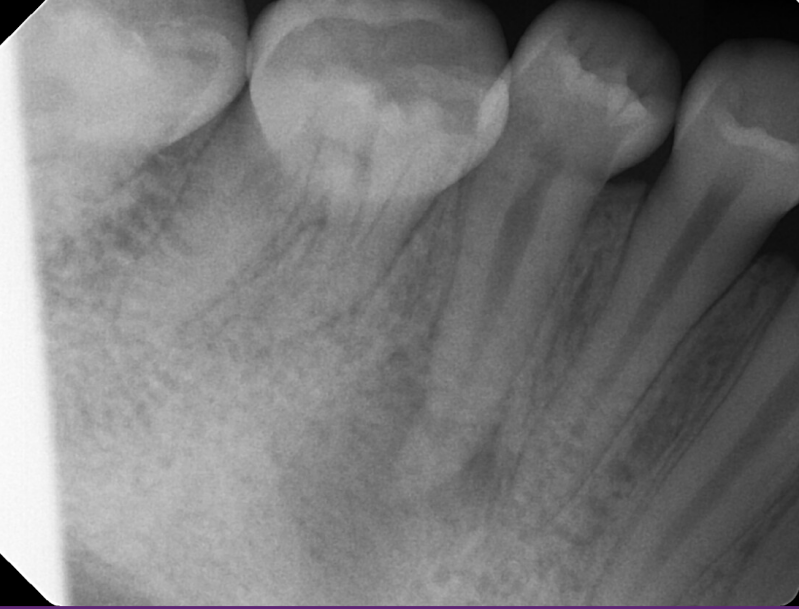

Case: RCT on Tooth #19

45-year-old female with complex medical history (anemia, ulcerative colitis, PTSD, GAD, etc.).

CC: Pain of unclear etiology.

Dx: Symptomatic irreversible pulpitis and symptomatic apical periodontitis.

Tx: RCT after informed consent regarding possible crack.

Outcome: Pain relief following treatment.

Reflection

Challenging diagnosis with unclear etiology. Access was complicated by pulp stones, which were successfully removed. Patient has remained asymptomatic since treatment.